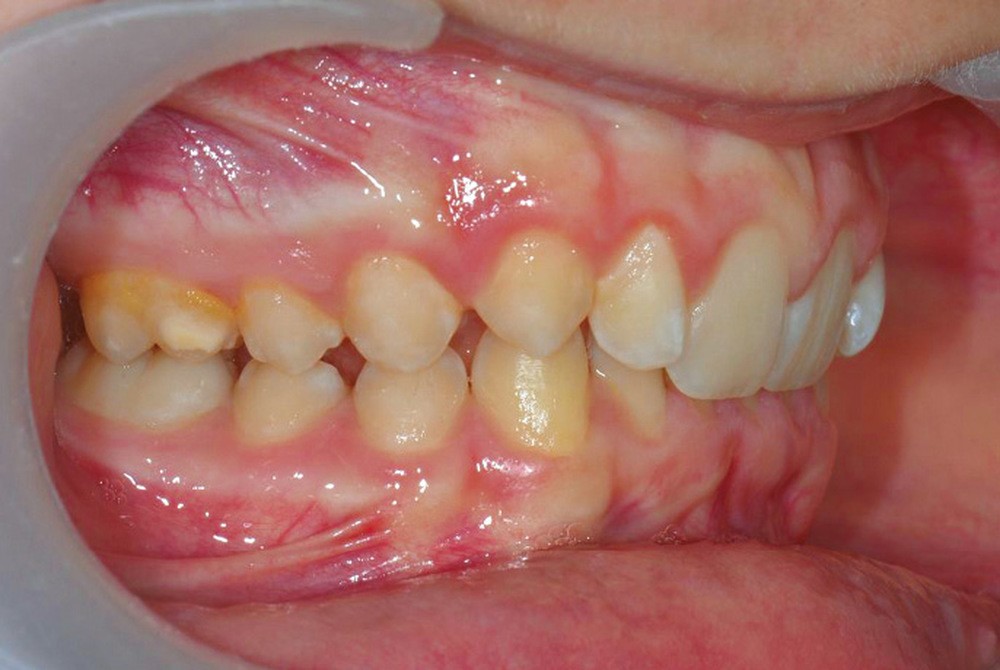

Son profil convexe s’inscrit dans un contexte de classe II squelettique par rétrognathie mandibulaire normodivergente sur un schéma de Classe II/2 avec supraclusion et encombrement modéré (fig. 1 à 7).

Le parodonte est de type 1 selon la classification de Maynard et Wilson.